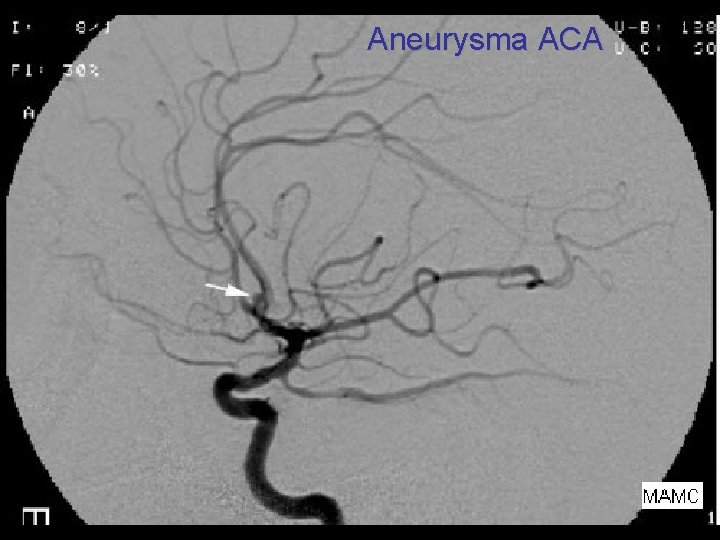

Aneurysma ACA